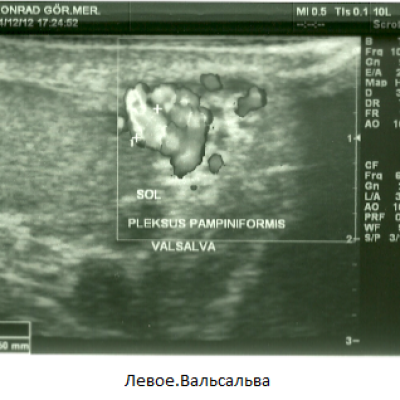

Мужу сделали УЗИ. Доктор сказал, что у мужа двустороннее варикоцеле. Нужна операция. Вот результаты УЗИ:

Заметно расширены вены левого гроздевидного сплетения и извилистость. Максимальный диаметр вен в расслабленном состоянии 2.09 мм., при проведении пробы Вальсальве 3,50 мм. В положении лежа при проведении пробы Вальсальве количественное увеличение венозных структур, увеличение диаметра до патологического размера. В режиме ЦДК, при проведении пробы Вальсальве был выявлен кровоток в обратном направлении - рефлюкс .

Фото тоже я прикрепила